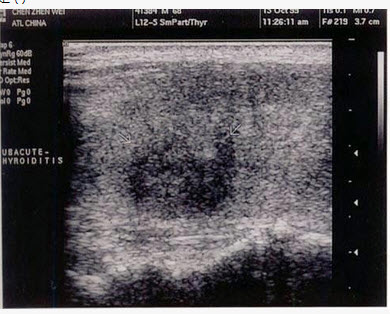

患者低热,咽喉肿痛1周。发现甲状腺肿大,左侧局部压痛,结合超声声像图,最可能的诊断是()

- A: 结节性甲状腺肿

- B: 亚急性甲状腺炎

- C: 甲状腺瘤

- D: 甲状腺癌

- E: 甲状腺功能亢进